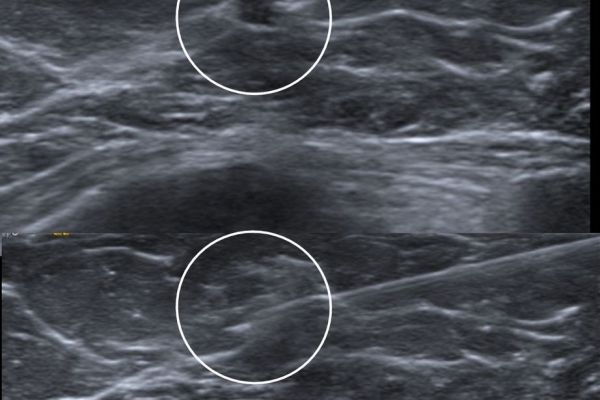

Σε περίπτωση που απαιτείται η χειρουργική αφαίρεση ενός ευρήματος που δε ψηλαφάται από το χειρουργό, τότε γίνεται η τοποθέτηση αγκίστρου σήμανσης (hook) λίγο πριν το χειρουργείο. Το άγκιστρο έχει σκοπό να καθοδηγήσει το χειρουργό για την αφαίρεση του σωστού τμήματος του μαστού, ώστε να αφαιρεθεί με ασφάλεια η ύποπτη βλάβη χωρίς να επηρεασθεί η αισθητική εικόνα του μαστού, πράγμα πολύ σπουδαίο ειδικά σε νέες γυναίκες και σε γυναίκες με μικρό μαστό.